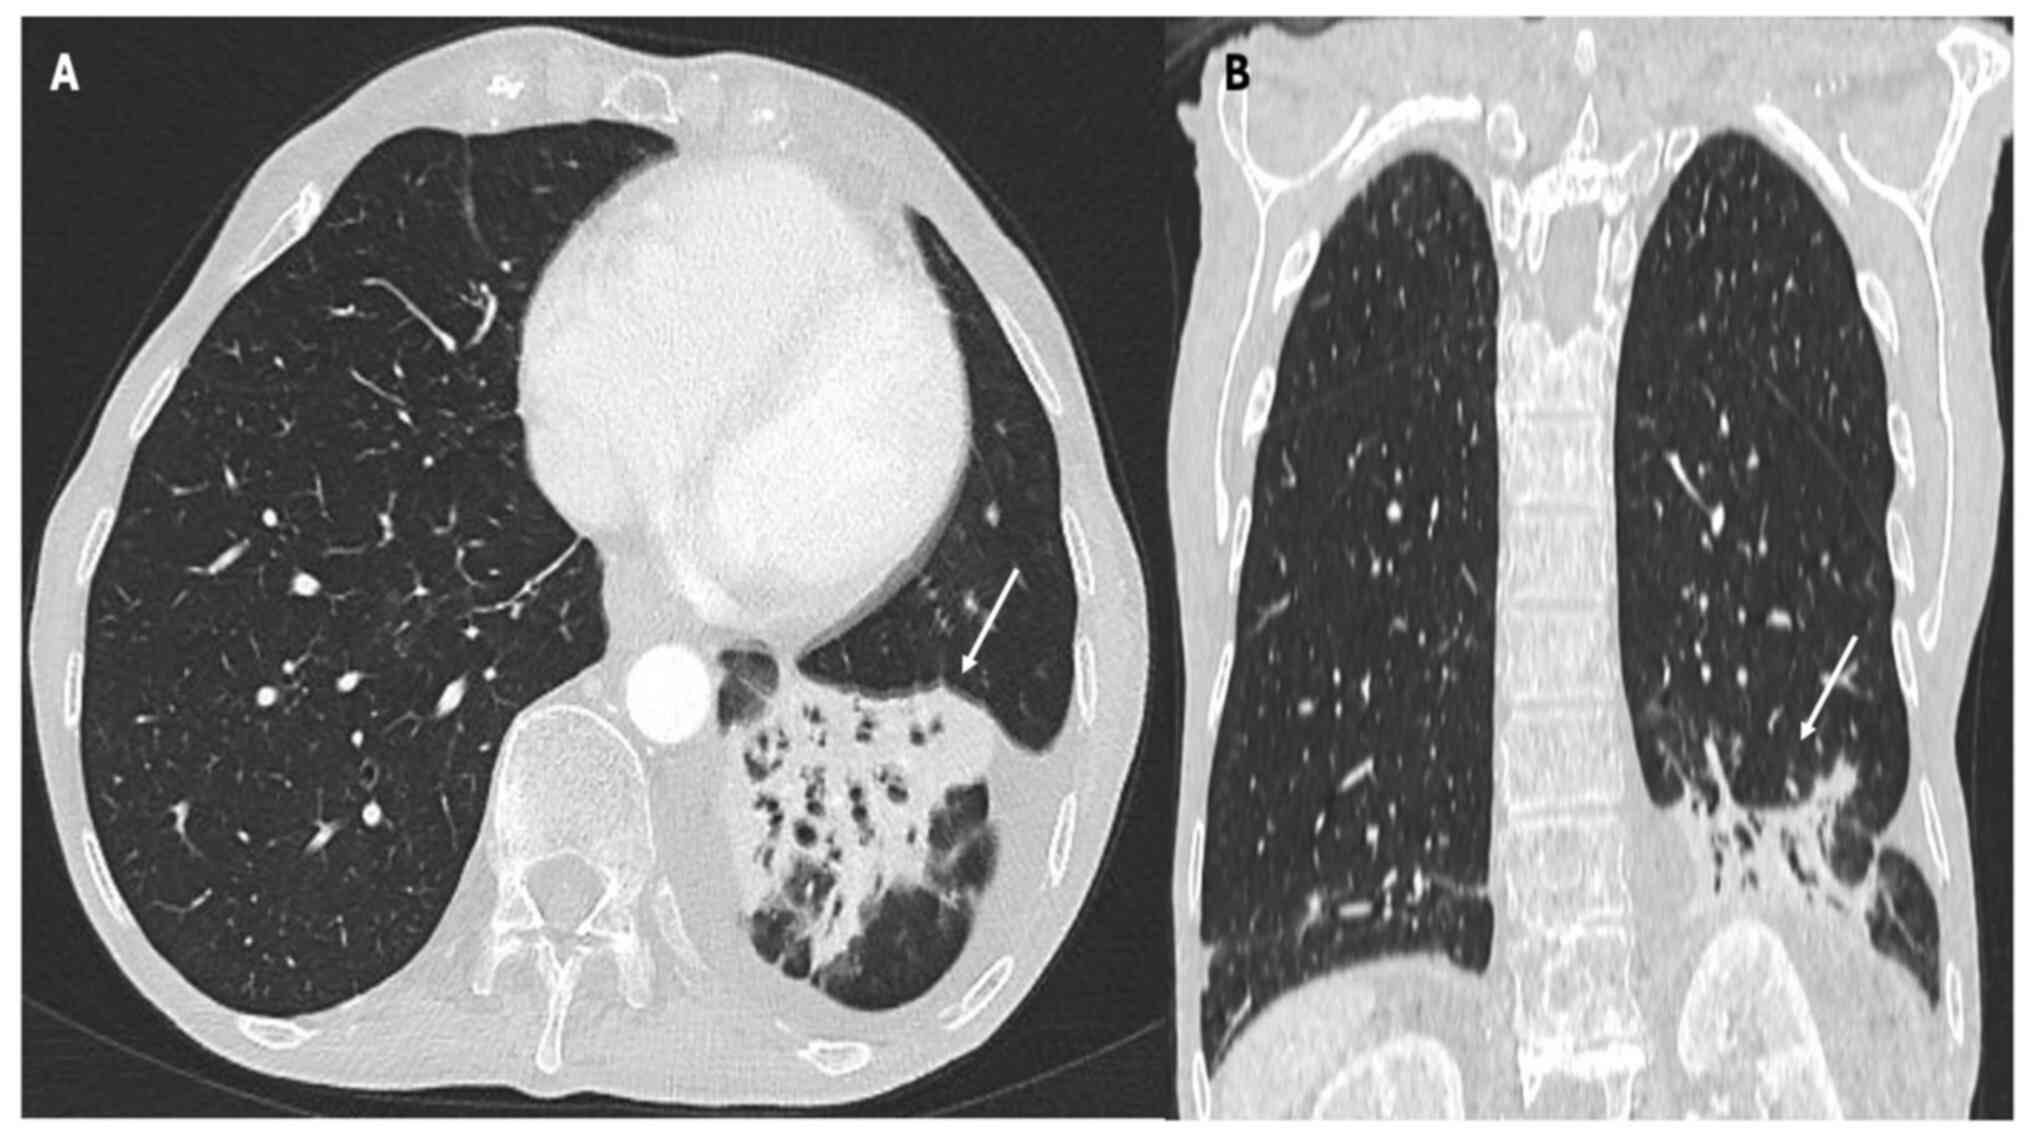

Pneumonitis is a rare irAE following ICI therapy, and it manifests as interstitial lung disease (36). Table II summarizes the main CT patterns observed in ICI-related pneumonitis. Pneumonitis secondary to ICI treatment presents in four distinct patterns: i) Organizing pneumonia (OP); ii) nonspecific interstitial pneumonia (NSIP); iii) hypersensitivity pneumonitis (HP); and iv) diffuse alveolar damage (DAD) (36). While chest X-ray findings in ICI-related pneumonitis may be nonspecific, characteristic abnormalities can aid the diagnostic process (37). Common radiographic manifestations include patchy or diffuse opacities, consolidations and interstitial infiltrates, which may be bilateral and involve multiple lung lobes (37,38). Additionally, air bronchograms or a ‘ground-glass’ appearance may suggest alveolar involvement and inflammatory changes within the lung parenchyma as shown in Fig. 2, Fig. 3 and Fig. 4, which report on a case of gastric, lung and rectal cancer, respectively. However, it is essential to recognize that chest X-ray findings alone may not be sufficient to diagnose or exclude pneumonitis (37) definitively. Further imaging with CT of the chest is often necessary to delineate the extent and nature of pulmonary abnormalities and guide subsequent management decisions (38).

Figure 2

(A) Axial and (B) coronal CT scan with lung parenchyma reconstruction demonstrating consolidation in the left lower lobe characterized by air bronchograms (see arrows). The image is from a 52-year-old patient undergoing therapy with nivolumab for locally advanced gastric cancer.